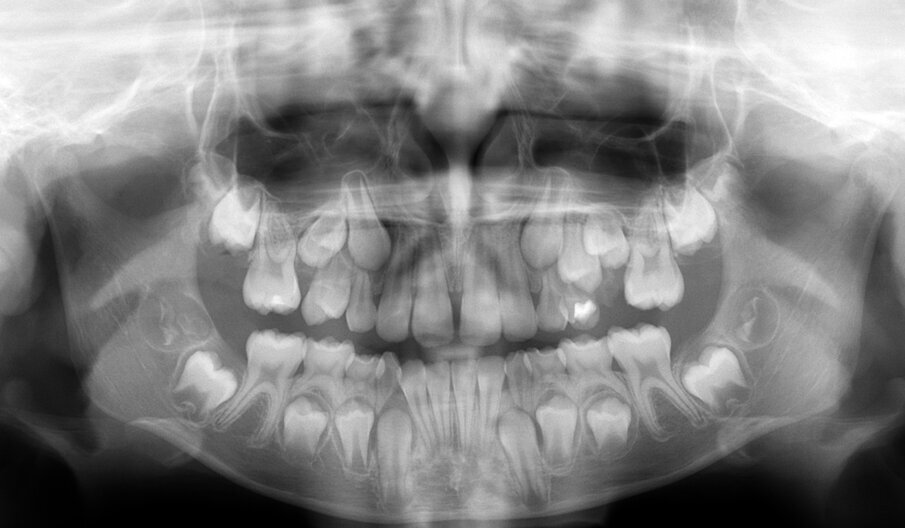

È importante ricordare che la lesione traumatica e/o cariosa può essere responsabile di patologie ascessuali e della perdita precoce di spazio in arcata, influendo negativamente sulla formazione e sull’eruzione del corrispondente elemento permanente. Necessario, pertanto, prevenire e curare tali evenienze, anche qualora si debba intervenire con trattamenti endodontici su elementi della serie decidua, affinché mantengano la propria integrità anatomica fino al completamento della permuta. Per eseguire un adeguato trattamento bisogna tenere in considerazione delle sostanziali differenze anatomiche e strutturali esistenti tra dentizione decidua e permanente che condizionano le situazioni patologiche del bambino. Le corone hanno una forma panciuta e tozza caratterizzate da uno smalto più sottile con uno spessore uniforme e dentina meno spessa.

Il tipo di contatto, inoltre, che si stabilisce tra un dente e quello adiacente non è identificabile in un punto, come avviene tra i denti permanenti, ma è rappresentato da una superficie. L’anatomia pulpare si presenta ampia rispetto alle dimensioni coronali, con cornetti pulpari più pronunciati. Tutte queste variabilità anatomiche rendono gli elementi decidui facilmente esposti a trattamenti endodontici, in seguito a processi cariosi.

Esiste un fenomeno fisiologico di tipo dinamico che interessa le radici degli elementi decidui e che non riguarda invece i permanenti. Il riassorbimento di un deciduo permette l’esfoliazione dell’elemento ed è un processo concomitante e correlato all’eruzione del corrispondente permanente. Tale processo fisiologico, chiamato anche rizalisi, è fondamentale e deve essere tenuto in considerazione quando si deve eseguire un trattamento endodontico dell’elemento deciduo. L’odontoiatra pediatrico deve tener conto che nella maggior parte dei casi si trova di fronte a elementi decidui che sono nella fase di regressione, e ciò comporta di dover utilizzare durante i trattamenti endodontici esclusivamente materiali riassorbibili.